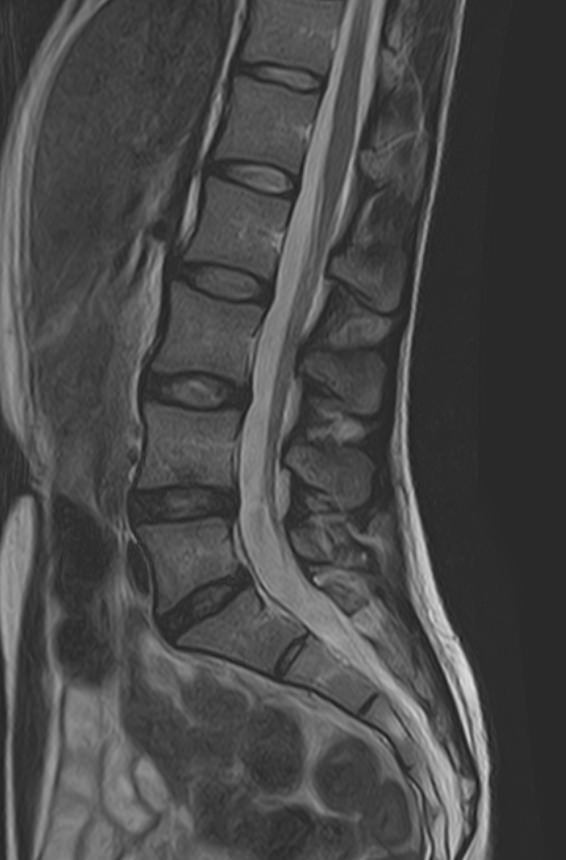

Боль в нижней части спины является наиболее распространенным симптомом различных заболеваний позвоночника, которые поражают пояснично-крестцовый отдел. В ряде случаев боли в нижних отделах спины сочетаются с кокцигодинией, то есть болями в рудиментарной части позвоночного столба – копчике. Причинами появления таких симптомов могут быть воспалительные процессы, дегенеративно-дистрофические заболевания позвоночника, опухолевые поражения данной анатомической области.

МРТ является наиболее информативным способом диагностики заболеваний позвоночника, так как позволяет оценить состояние костных структур позвонков, расположенную здесь часть спинного мозга с нервными корешками, а также связки, сухожилия и окружающие мягкие ткани. Магнитно-резонансная томография превосходит все другие методы диагностики не только по информативности, но и по безопасности, так как в основе метода лежит использование внешнего магнитного поля и отсутствует вредное для организма воздействие облучения, свойственное рентгену.

Для выявления причин появления кокцигодинии и болей в нижней части спины в клинике «Доступная медицина» проводится комплексное обследование МРТ пояснично-крестцового отдела + копчик, включающее два протокола исследования каждой анатомической области.